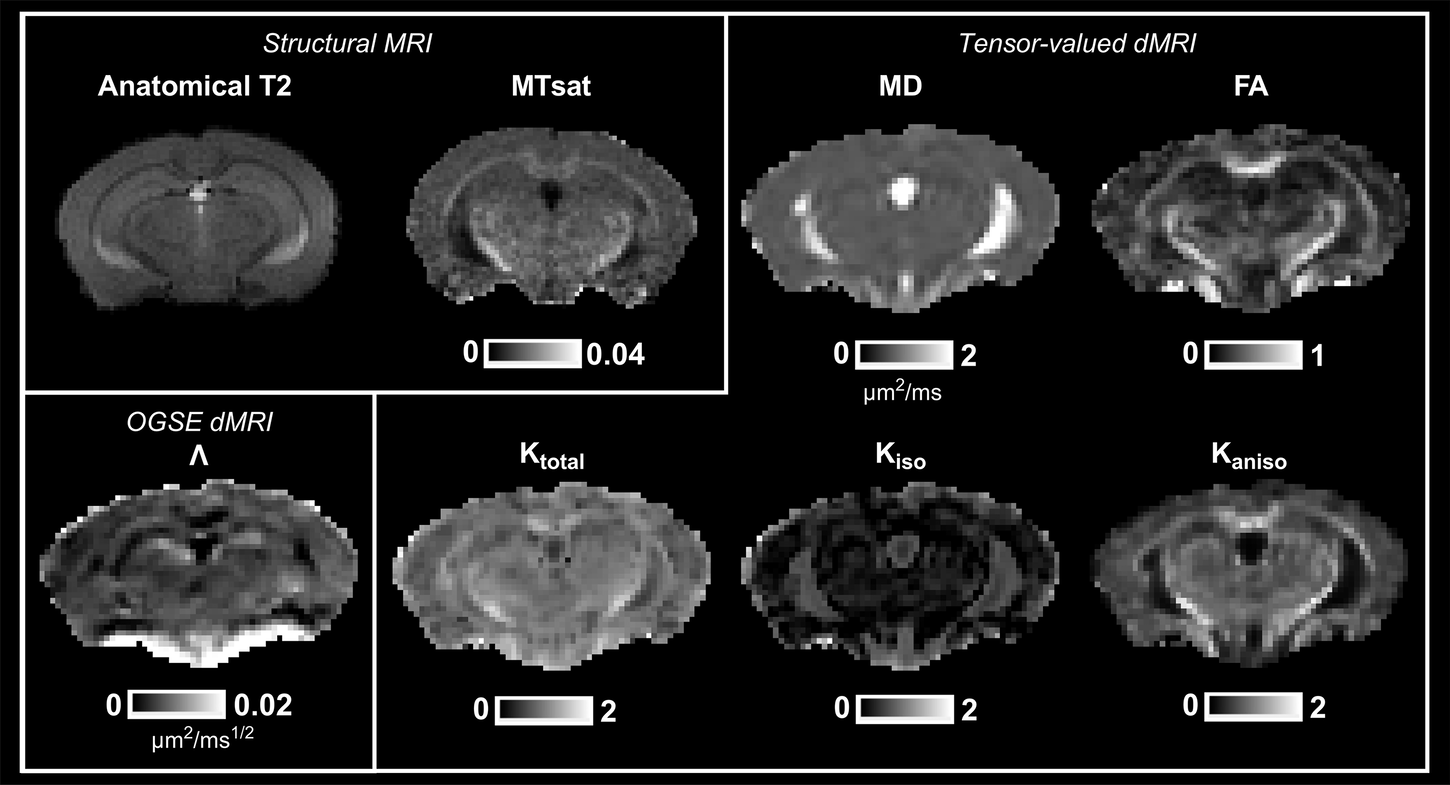

Fig. 1: Representative axial parameter maps from one mouse at 3 months of age.

Structural maps include T2-weighted and MTsat (magnetization transfer saturation). Maps from the OGSE dMRI protocol include \(\Lambda\) (the diffusion dispersion rate). Maps from the tensor-valued dMRI protocol include MD (mean diffusivity), FA (fractional anisotropy), Ktotal (total kurtosis), Kiso (isotropic kurtosis), Kaniso (anisotropic kurtosis).